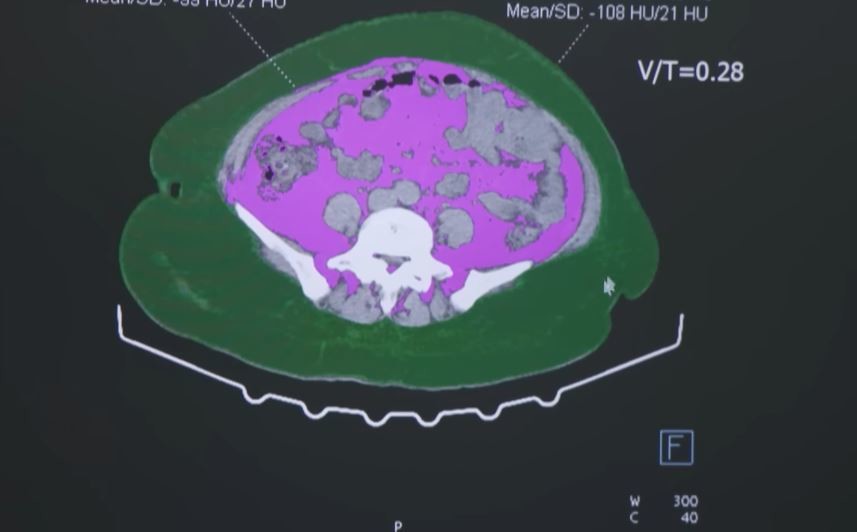

◆ 비만이 무서운 이유… 체중보다 ‘몸 속 변화’

비만은 단순히 체중이 늘어난 상태가 아니다. 지방세포가 늘어나면서 인슐린 저항성이 생기고, 혈압과 콜레스테롤 수치가 함께 상승한다. 이로 인해 당뇨병과 고혈압, 심근경색, 뇌졸중 등 각종 심혈관 질환의 위험이 커진다.

또한 과도한 지방은 염증 반응을 유발해 암의 발생률을 높인다. 유방암, 대장암, 간암, 췌장암 등은 모두 비만과 밀접한 관련이 있다. 최근 연구에서는 ‘지방이 호르몬 분비 기관처럼 작용한다’는 사실이 밝혀지면서, 비만이 전신 질환의 출발점이라는 인식이 강화되고 있다.